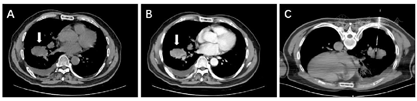

入院后复查胸部CT检查显示右肺下叶一浅分叶状肿块,肿瘤最大径约4.4 cm,增强扫描呈不均匀明显强化(图1A,B);右侧胸膜结节状增厚、强化;右肺中下叶、右侧心缘旁、右侧叶间裂可见多发结节,强化不均匀;右侧第3、4、7、8肋骨骨质破坏;右侧膈下、心膈角区、右侧膈肌可见多发肿大淋巴结,强化不均匀。CT结果提示右下肺癌可能,并肺内、胸膜、右侧多处肋骨及多发淋巴结转移。为明确诊断,遂行CT引导下经皮右肺下叶肿块穿刺活检(图1C)。